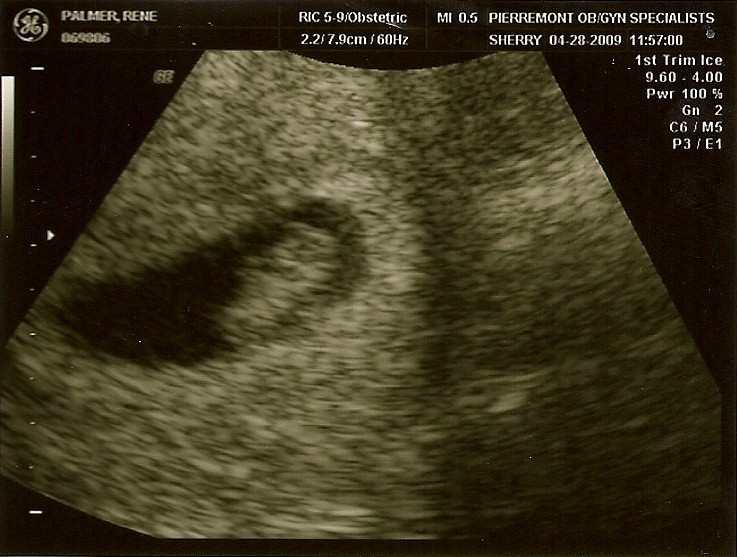

8. Hafta Anne Karnı Bebek Ultrason Görüntüleri